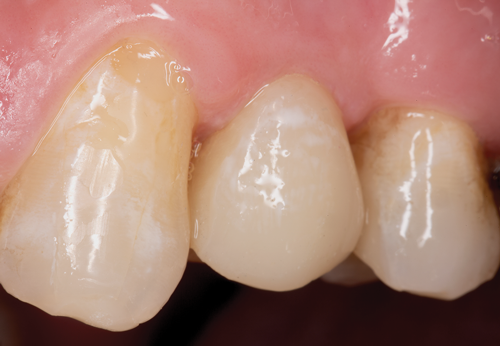

Fig 3. After endodontic treatment, crown lengthening was performed to develop an ideal ferrule effect.

Figure 3

Fig 4. An adequate collar effect of 2 mm of sound tooth structure would provide an anti-rotational feature for the stability of the crown.

Figure 4

Fig 5. Buccal view of optimal ferrule effect with a healthy biological framework.

Figure 5